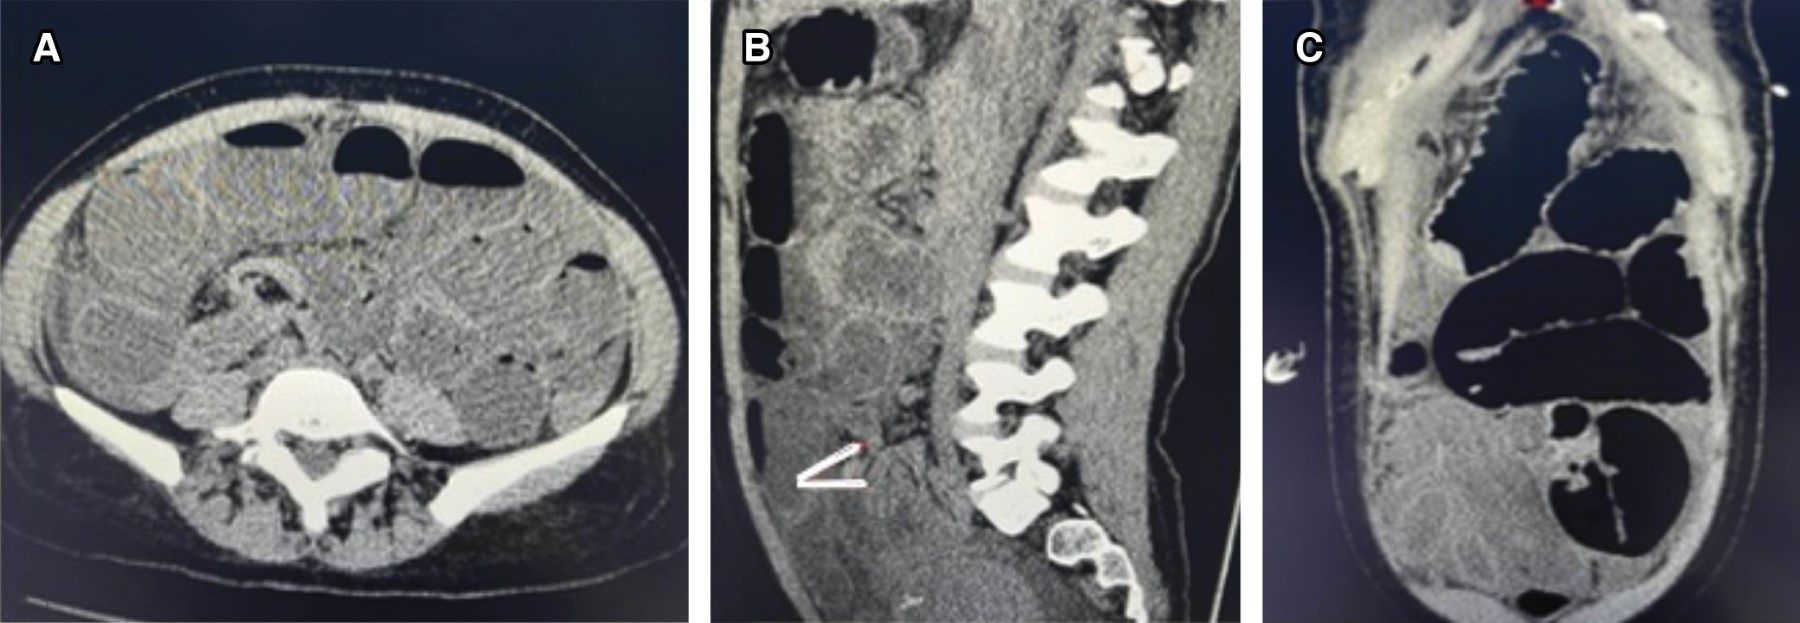

Figure 3